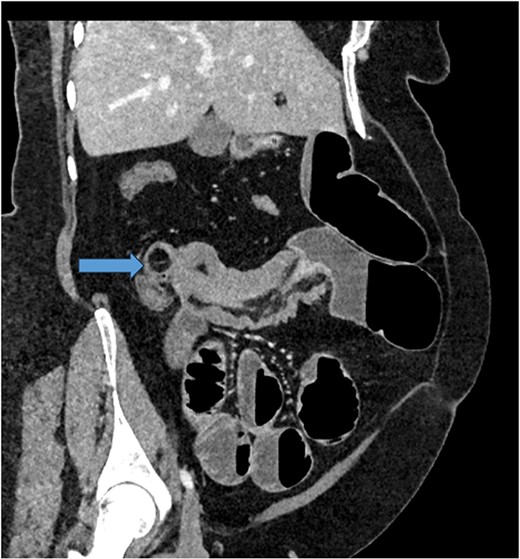

Given her abdominal symptoms and signs, she was subjected to an abdominal X-ray (Fig. 1), which showed multiple distended loops of the small bowel, and a chest X-ray, which showed left basal atelectasis. A working diagnosis of SBO was made. She was put nil by mouth. A nasogastric tube and a urinary catheter were inserted. After initial resuscitation, she was subjected to CTAP with contrast. The findings of the CTAP were in keeping with acute distal SBO secondary to an ileo-ileal intussusception. No obvious mucosal mass was stated in the initial report (Figs 2 and 3).

CT scan of abdomen: oblique coronal view of abdomen showing intussusception with low attenuation lesion distally C/W a lipoma (arrow).